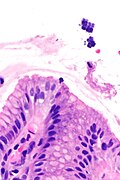

Micrograph showing Sarcina. H&E stain. (WC/Librepath)

Sarcina organisms are occasionally seen in the gastrointestinal tract. They are reported in urine.[1]

Features:[3]

- Small essentially spherical micro-organisms.

- Each micro-organism 1.8-3 micrometres - purple on H&E stain.

- Arranged in clusters of 4, 8 or more - classically in a tetrad - key feature.